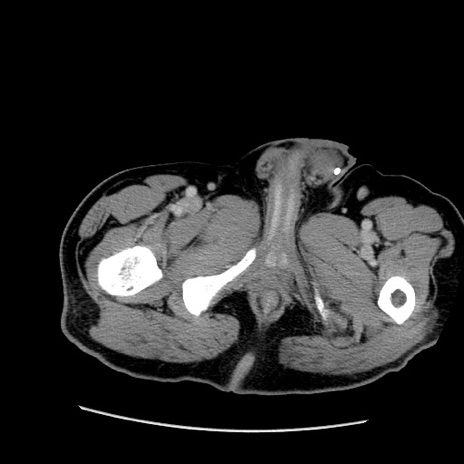

症例22(横断像)

【症例】50歳代男性

【主訴】腹痛

【現病歴】AVMからの被殻出血のため回復期リハ病棟入院中。 本日午後3時頃急に下腹部痛が出現した。

【既往歴】AVM、被殻出血、虫垂炎、高血圧

【身体所見】意識晴明、左半身不全麻痺、会話の理解は良好、36.5°C、腹部:膨隆、全体に板状硬、下腹部正中に圧痛点あり、反跳痛-、筋性防御不明、右下腹部にope scar

【データ】WBC 9400、CRP 0.06